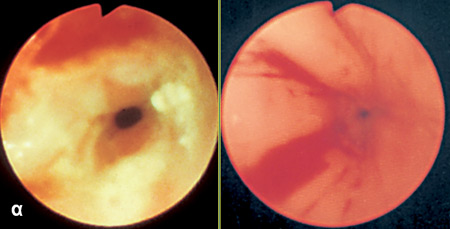

ΙV. Είναι αναμφισβήτητη η διαγνωστική και επεμβατική αξία της οισοφαγοσκόπησης.

Επιπλέον, η οισοφαγοσκόπηση αποκαλύπτει "εικόνες" όπως διαβρωτικής

οισοφαγίτιδας ή εγκαύματος από κατάποση καυστικών ουσιών (εικόνα 5).

EIKONA 5. Διαγνωστική και

θεραπευτική ενδοσκόπηση. α. Διαβρωτική οισοφαγίτις. β. Διαστολή στενώσεως οισοφάγου

με μπαλόνια. γ. Έγχυση σκληρυντικής ουσίας σε κιρσούς.